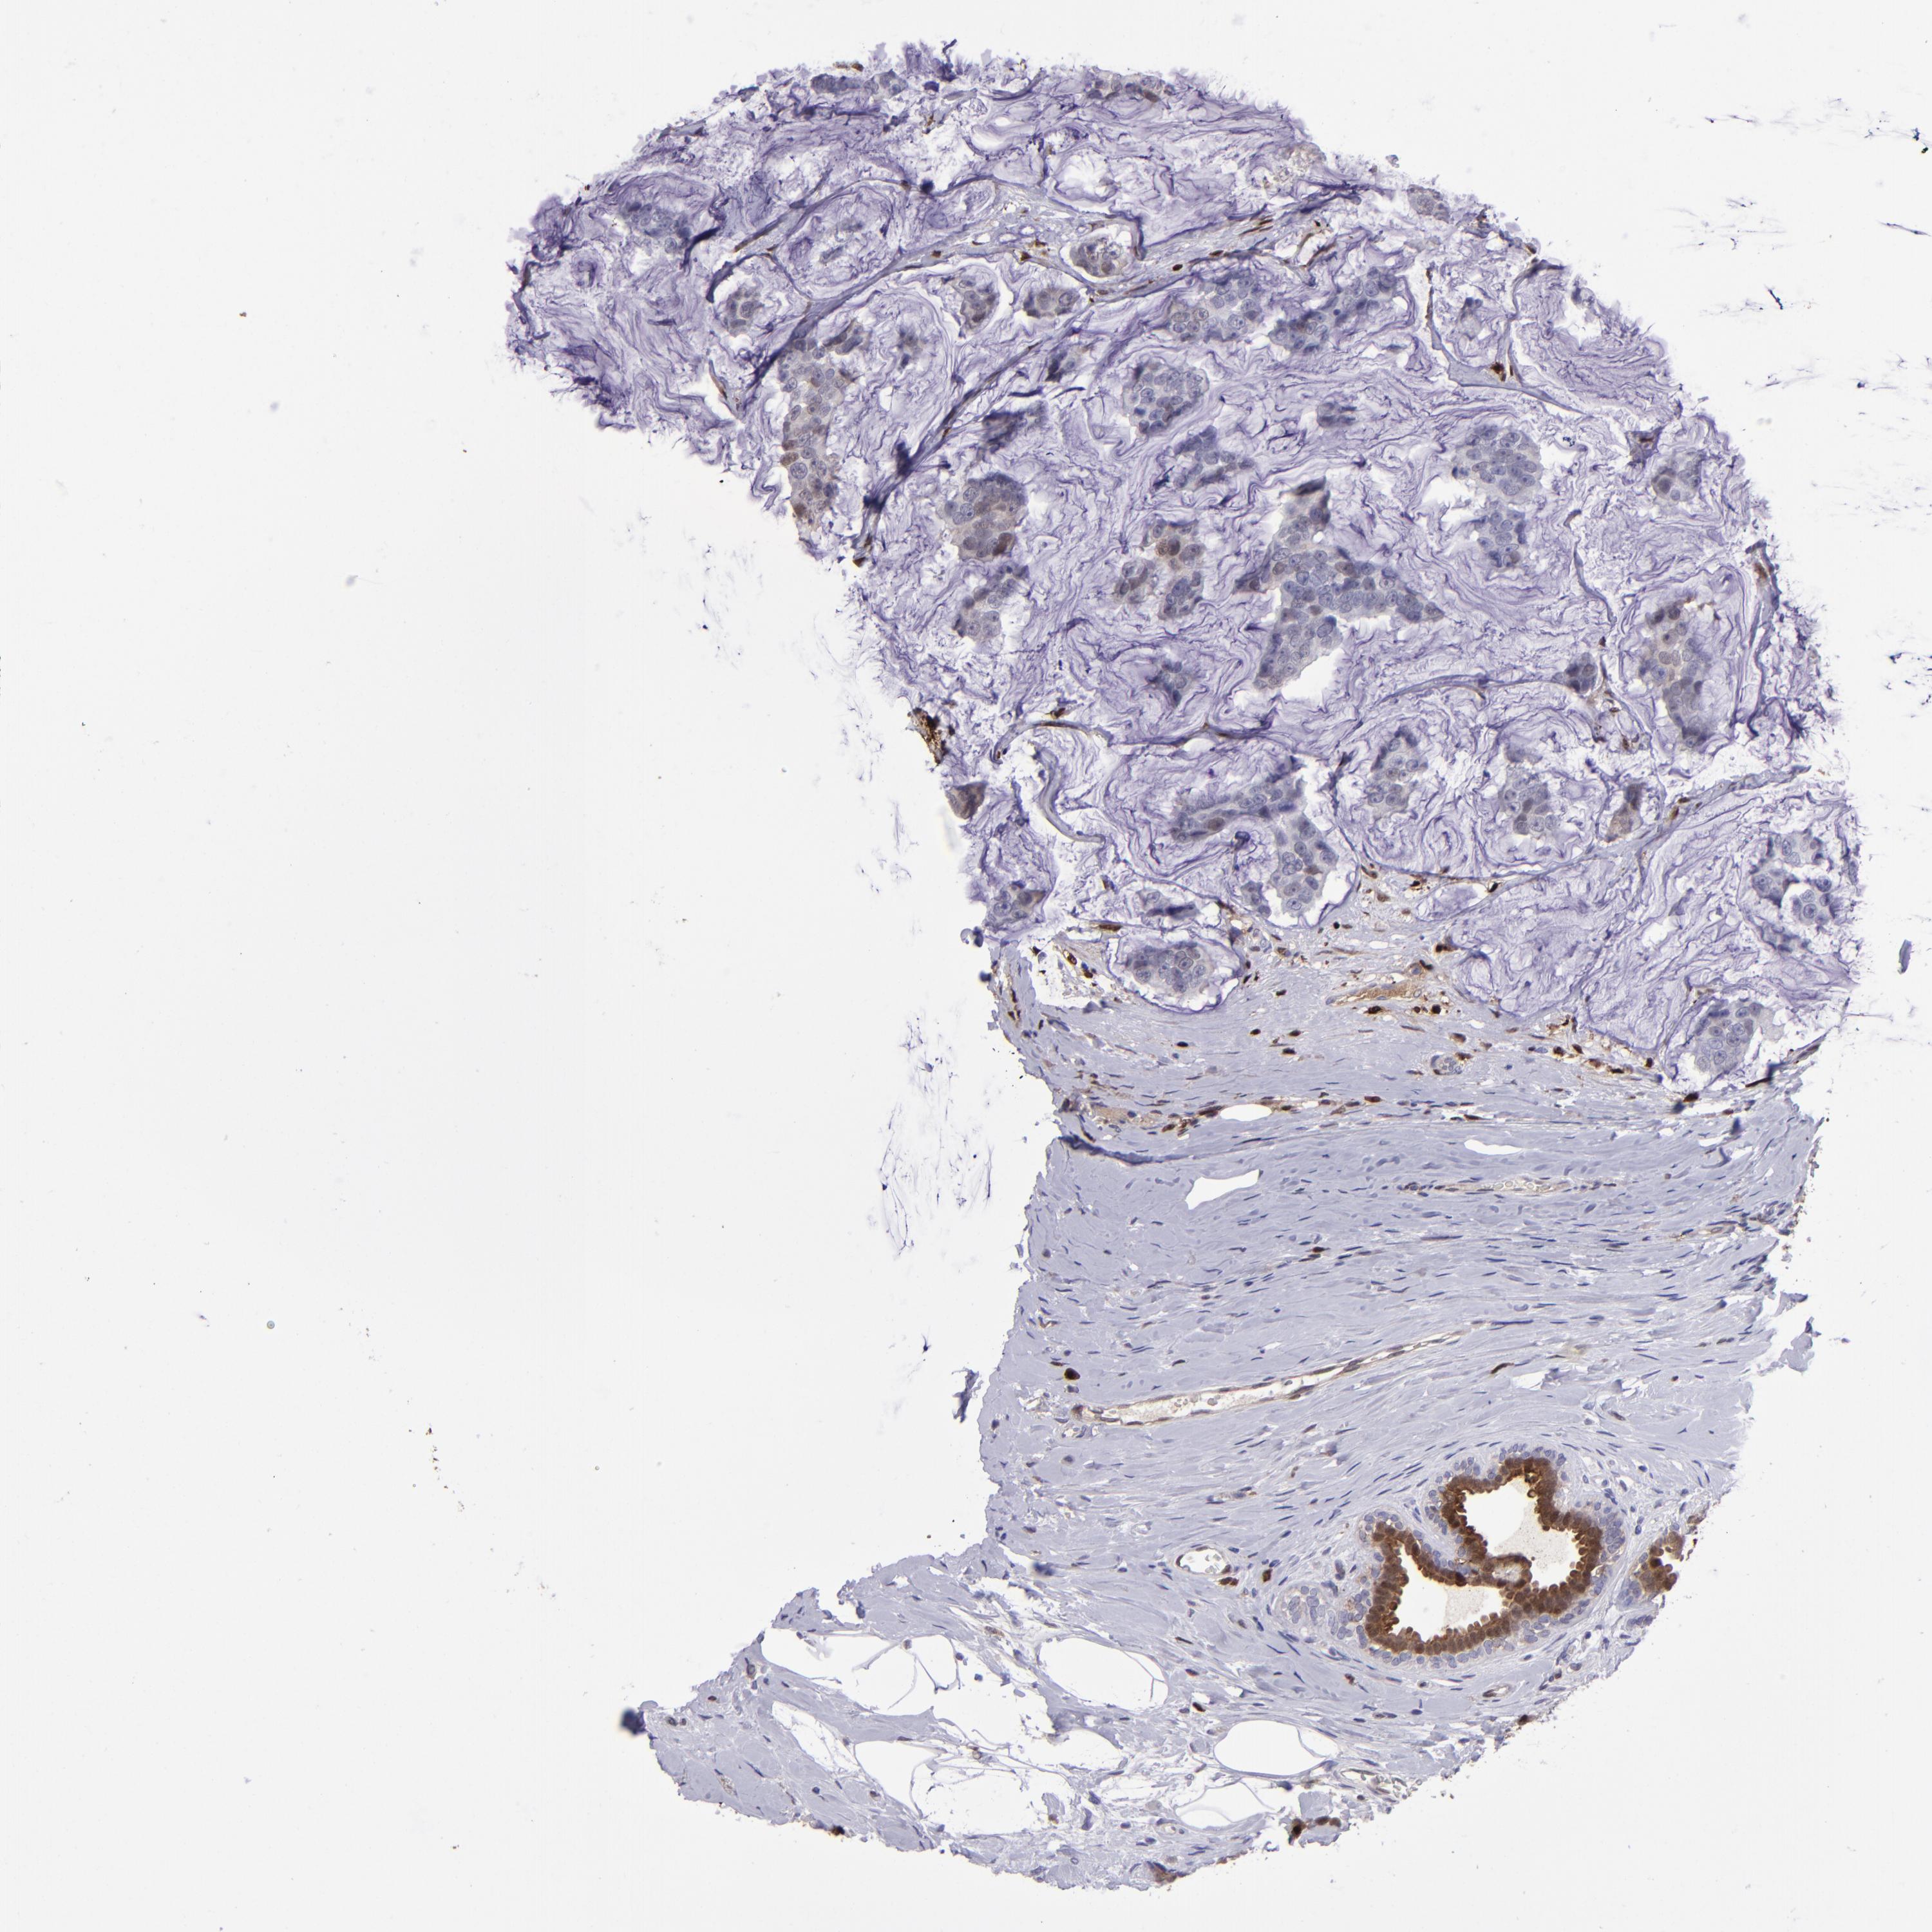

BRCA TCGA BRCA VALIDATION PROTEIN EXPRESSION

ANTIBODIES

AND

VALIDATION